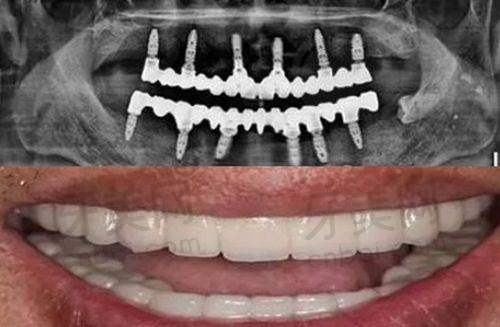

深圳福田徕可口腔(理想城)开展的口腔诊疗项目十分齐全。其中种植牙项目备受关注,包括微创种植牙、前牙美学种植、all - on - 4/6半全口即刻负重种植、上颌窦内外提升种植等。对于牙齿缺失的患者来说,种植牙可以良好地修复牙齿的功能和美观,就像拥有了自己的真牙一样。